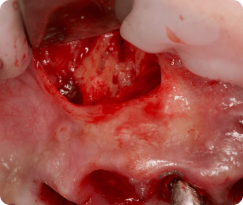

Удаление ретенированных и дистопированных третьих моляров

Что будет в модуле:

Атравматичное удаление ретенированных третьих моляров

Классификация ретенции третьих моляров

Разрезы и типы лоскутов

Техника остеоэктомии

Навыки на уровне челюстно-лицевой хирургии: от удаления зачатка ретенированного нижнего третьего моляра до удаления горизонтально расположенных зубов.